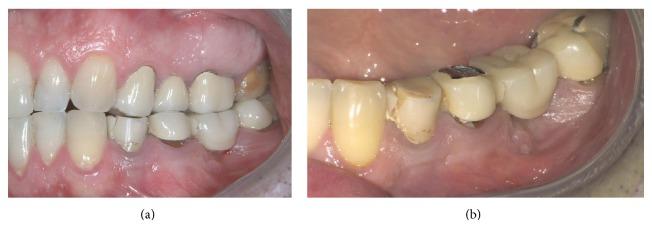

The extraction of teeth results in rapid bone resorption both vertically and horizontally in the first month. The loss of alveolar ridge reduces the chance of implant rehabilitation. Atraumatic extraction, implant placement in extraction socket, and an immediate prosthesis have been proposed as alternative therapies to maintain the volume and contours tissue and reduce time and cost of treatment. The immediate load of implants is a universally practiced procedure; nevertheless a successful procedure requires expertise in both the clinical and the reconstructive stages using a solid implant system. Excellent primary stability and high bone-implant contact are only minimal requirements for any type of implant procedure. In this paper we present a case report using a new type of implants. The new type of implants, due to its sophisticated control system of production, provides to the implantologist a safe and reliable implant, with a macromorphology designed to ensure a close contact with the surrounding bone.